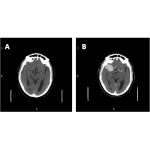

Top tips for imaging in hyperacute stroke

Acute ischaemic stroke (AIS) is the second leading cause of death and the third cause of death and disability worldwide. The estimated global cost of stroke is over $720 billion. In the UK, the incidence of stroke is over 110,000 and the prevalence of stroke is predicted to increase by 120% by 2035. Hyperacute stroke […]